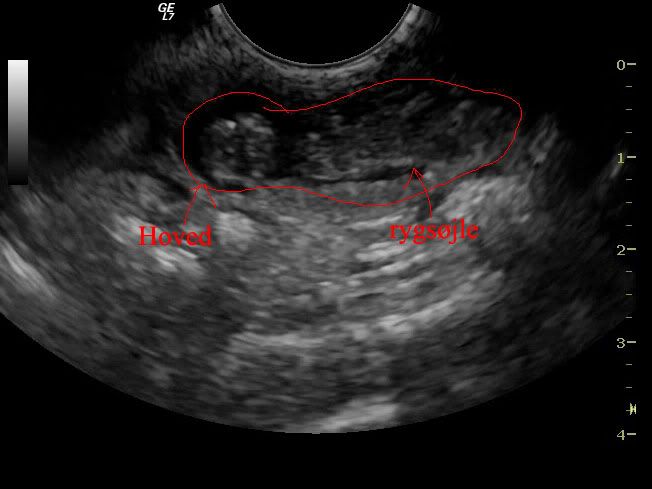

Her er en lille hvalp :D

Og her har jeg tegnet rundt om den så folk kan navigere

og endnu en :D

med streger

Og så nok det bedste screenshot jeg kunen tage, jeg synes den er ret tydelig :D Den ligger med ryggen til